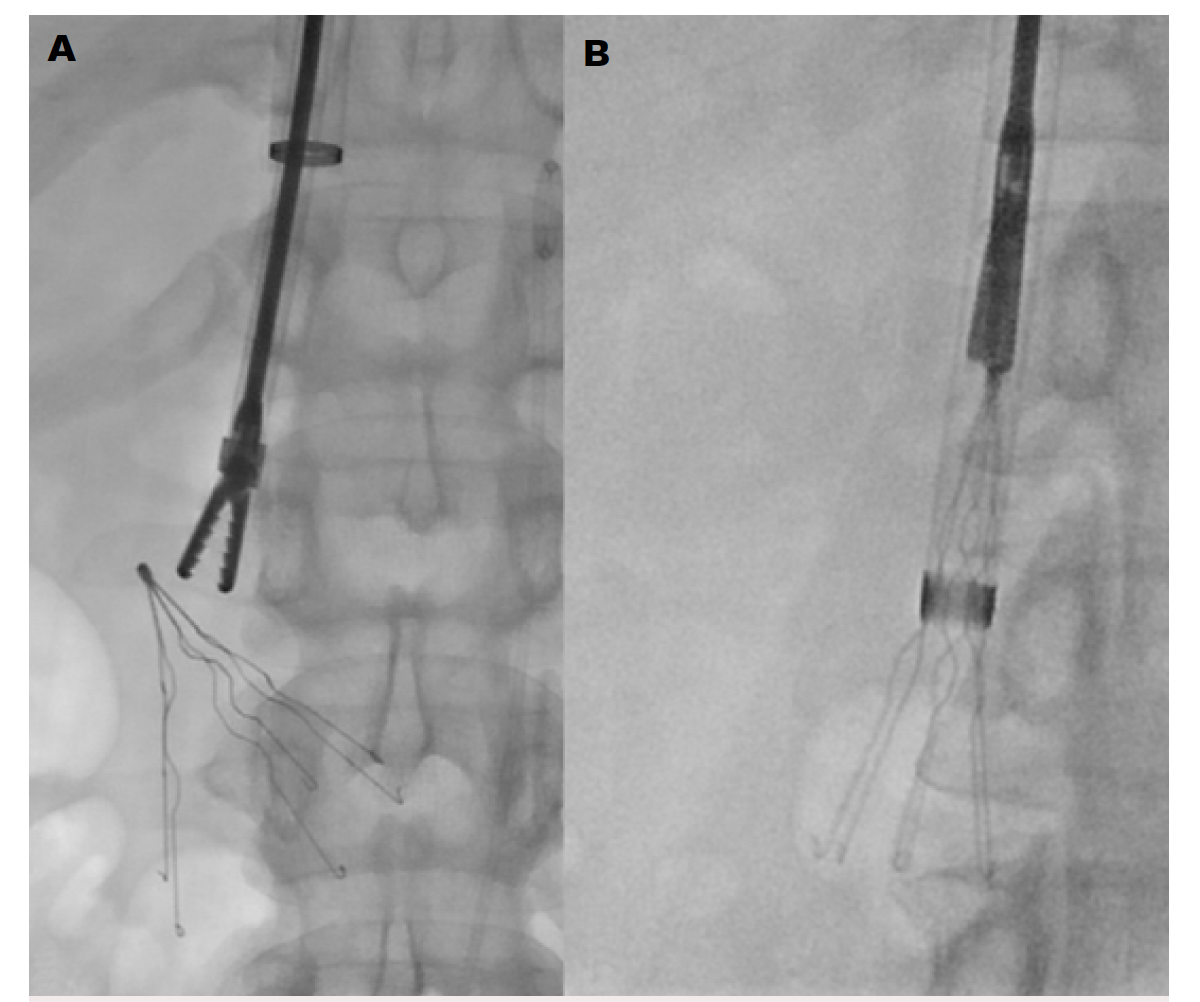

Endobronchial/Endoscopic Forceps

The forceps technique for filter retrieval has a significant benefit in patients where the tip or hook is embedded in the IVC wall, thus limiting the ability to snare the top of the filter. This has often become a go-to option for advanced operators compared with wire-loop or hangman approaches. This is mostly because it can help avoid situations such as bending the proximal filter aspect, elongating the hook, filter strut fracturing, and loop wire breakage that is seen with the other techniques. However, it should be noted that use of forceps requires caution, and a certain level of experience, as novice users can easily find themselves in complications with misuse or unnecessarily aggressive maneuvers. The most-used endobronchial forceps is the Lymol 4162 (Lymol Medical), which is off-label, and can be advanced through a sheath ≥12 Fr; however, ≥16 Fr is recommended if using forceps to bring the filter into the sheath rather than just for fibrin maceration. Again, experience is beneficial when using rigid forceps, as haphazard use can cause significant complications including caval perforation, adjacent arterial damage, and twisting/intussusception of the IVC, which can be devastating. These forceps can be sterilized, and shaped as needed, to approach tilted filters. During its use, the forceps is mostly used to gently dissect the filter tip free from the fibrin cap coating, and once freed, can assist to move the filter away from the wall (Figure 1). Once the forceps’ teeth contact the metal tip/hook of the filter, it is used to maintain gentle traction on the filter while the remainder of the filter is captured by advancing the sheath; again, the filter should never be pulled up completely.